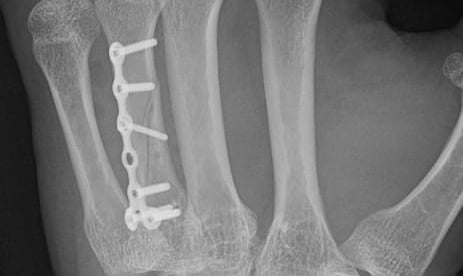

Fracturas y secuelas